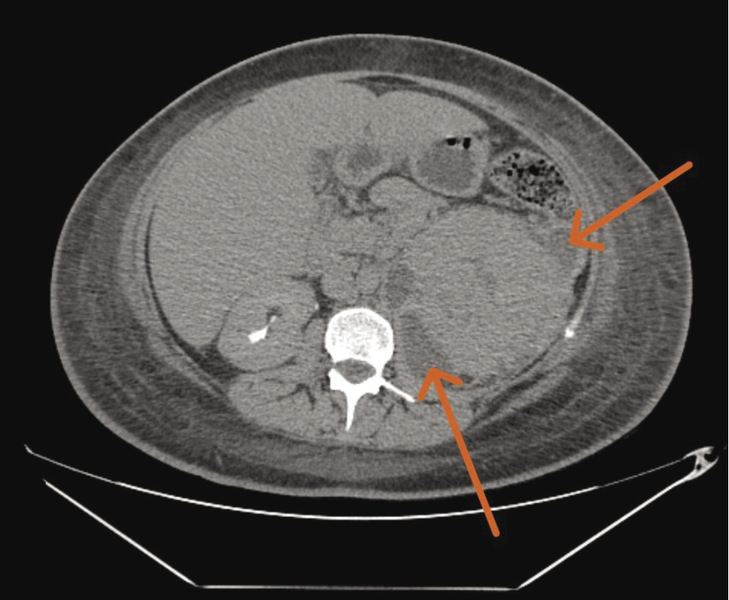

W trzeciej dobie pobytu na oddziale diagnostykę poszerzono o 4-fazową TK jamy brzusznej. Na jej podstawie stwierdzono utrzymujące się powiększenie lewej nerki, bez widocznego zróżnicowania miąższu, z prawdopodobnymi obszarami rozpadu (ryc. 2). Nerka otoczona była płynem oraz pogrubiałymi blaszkami powięzi. Dostrzeżono ponadto zbiornik płynowy wielkości 33 × 17 × 48 mm w obrębie powiększonego lewego mięśnia lędźwiowego większego. Podobną zmianę o charakterze patologicznego zbiornika płynowego stwierdzono w okolicy zgięcia śledzionowego kątnicy. W posiewach krwi i moczu zaobserwowano wzrost bakterii Escherichia coli – szczep pozostawał wrażliwy na ceftriakson (dotychczasową antybiotykoterapię utrzymano).

Rycina 2. Obraz 4-fazowej tomografii komputerowej jamy brzusznej – badanie przeprowadzone w trzeciej dobie hospitalizacji